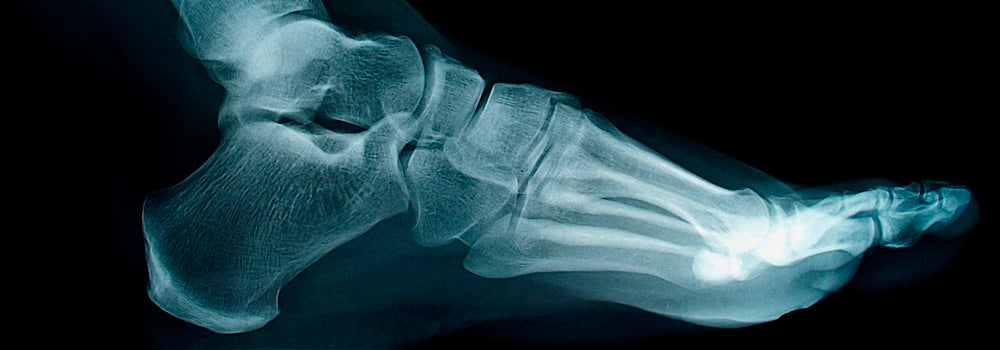

Плоскостопость, или снижение сводов стопы у ребенка требует немедленной реакции родителей. Консультации у врача, специальная гимнастика и правильная детская ортопедическая обувь – первые шаги к борьбе с плоскостопием. А чтобы избежать такой проблемы, необходимо устранять или предотвращать возможные причины ее появления (разумеется, при исключении врожденного плоскостопия). Поэтому сегодня мы перечисляем основные причины появления плоскостопия у детей:

3. Перенесенные травмы и переломы – вот причина травматического плоскостопия. Следите за тем, чтобы Ваш ребенок играл в безопасном месте, особенно это касается игр на улице с друзьями.